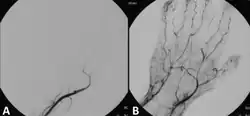

Angiograph before and after thrombolytic treatment of acute limb ischemia.

Endovascular interventions for ALI are minimally invasive procedures designed to quickly restore blood flow and avoid more extensive surgery. In endovascular interventions, a catheter is used to deliver medication such as thrombolytics to dissolve the clot. In the past, streptokinase was the main thrombolytic chemical. More recently, drugs such as tissue plasminogen activator, urokinase, and anistreplase have been used in their place. Mechanical methods of injecting the thrombolytic compounds have improved with the introduction of pulsed spray catheters—which allow for a greater opportunity for patients to avoid surgery.[21][22] Pharmacological thrombolysis requires a catheter to be inserted into the affected area, attached to the catheter is often a wire with holes to allow for a wider dispersal area of the thrombolytic agent. These agents lyse the ischemia-causing thrombus quickly and effectively.[23] However, the efficacy of thrombolytic treatment is limited by hemorrhagic complications. Plasma fibrinogen level has been proposed as a predictor of these hemorrhagic complications. However, based on a systematic review of the available literature until January 2016, the predictive value of plasma is unproven.[24] After the clot has been dissolved or removed, a stent or balloon may be placed to keep the artery open and prevent further ischemia.